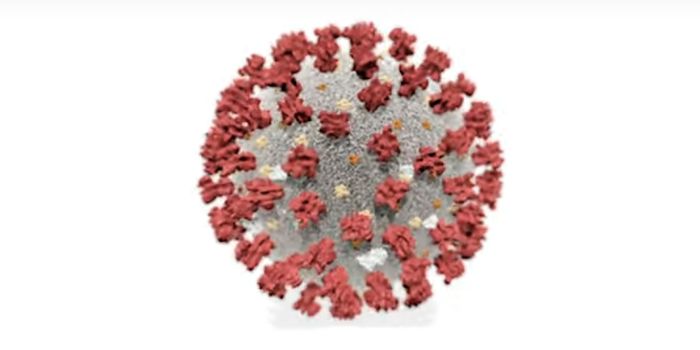

APR 27, 2020MicrobiologyThe pandemic virus that causes COVID-19 has now infected nearly 3 million people, and killed over 200,000.

MAY 10, 2021MicrobiologyThe pandemic virus SARS-CoV-2 has changed the world in devastating ways, taking hundreds of thousands of lives & new var ...

MAR 23, 2021Health & MedicineA pregnant woman infected with the pandemic virus SARS-CoV-2 passed the virus on to her unborn child through the placent ...

MAR 03, 2020MicrobiologyThere have now been nine deaths in the United States, all in Washington state from COVID-19, the illness caused by the n ...

APR 21, 2021ImmunologyGenetic variants of the SARS-CoV-2 virus have emerged and tightened their grip on global communities as the pandemic rag ...

NOV 01, 2020MicrobiologySARS-CoV-2, which causes COVID-19 has to get into cells to cause infection. It does so with a spike protein on its surfa ...